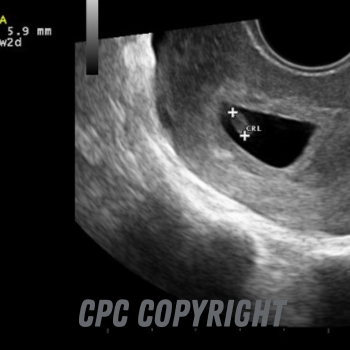

4 weeks after conception/6 weeks from your last period

4 weeks after conception the fetus (baby) will measure approximately 3 mm and will have a visibly beating heart. The heart beat can be measured by the ultrasound machine, and will produce an image showing wavy motion lines similar to an adult EKG.